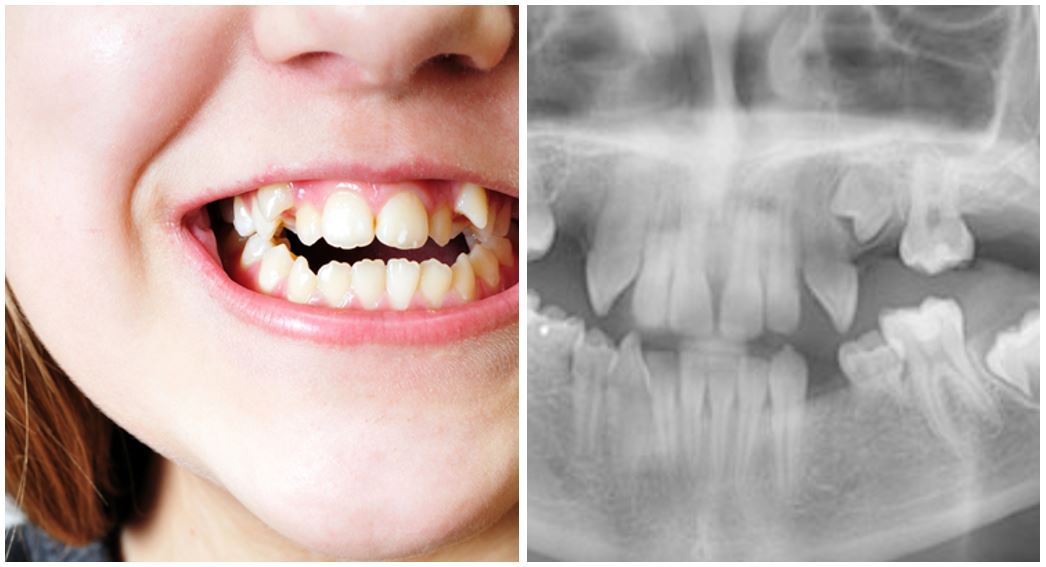

¿QUÉ TIPO DE MORDIDA TIENES?

Definir la belleza es muy difícil. Sin embargo, un rostro atractivo siempre se encuadra dentro de proporciones armónicas, con las variaciones personales y raciales de cada uno, donde las medidas [...]